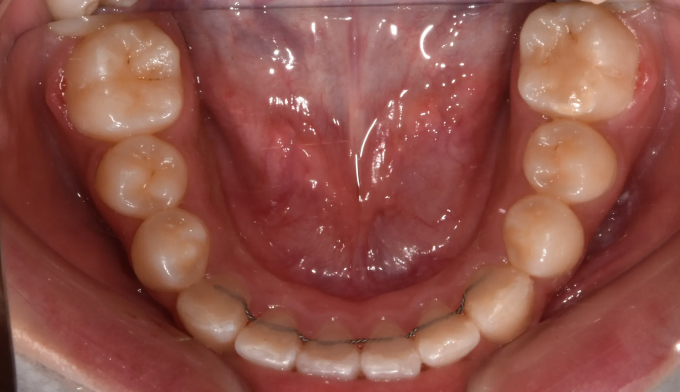

위턱, 아래턱 모두 치아 배열 공간이 부족한 경우 입니다.

확장장치를 이용해 공간 부족을 해결하고 치열을 배열하면 간단히 끝낼 수 있습니다.

이때 입술의 두께나 위치, 위아래 앞니의 각도를 종합적으로 고려하여야 합니다.

치아를 배열한다고 앞니가 뻐드러지면 잘못된 교정치료입니다.

총 치료기간은 20개월 소요되었습니다.